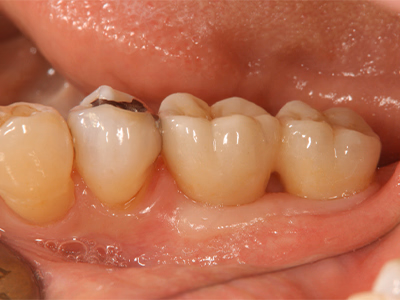

治療前後写真

治療前

治療後

20歳・女性

来院理由

銀歯が取れてしみる

治療内容

ルーペ下でカリエス除去

精密印象採得→後日セラミックインレーを強力接着

メンテナンス移行

治療期間

1日(装着は後日)

費用

35,000円

リスク・副作用

再補綴時に歯髄損傷リスク上昇

残存歯質が少ない場合は破折の可能性

医院コメント

適合・耐久性・審美性を重視したセラミックで金属露出を解消。